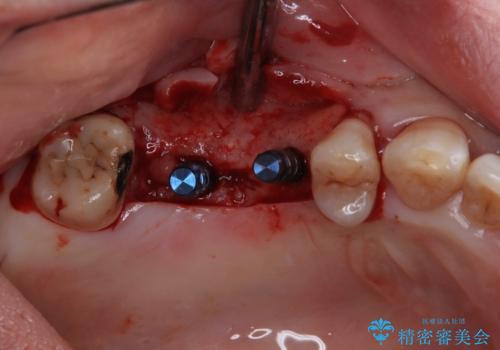

- インプラント治療を前提に下顎の部分矯正を始めたものの、そのまま長い間放置しているとのことで来院された患者様です。

全体的に歯肉が腫れており、歯周病により抜歯をしなければならない歯がある状態でした。

矯正治療を仕上げ、必要に応じて歯周外科処置を行い、適宜インプラントを埋入しながら咬み合わせを回復させていくこととしました。

治療前は磨き残しが多く見られ、全体的に歯肉が腫れている状態でしたが、抜歯の必要な歯を抜いたことで口腔内の環境が改善され、磨き残しも少なくなってきました。

インプラントにより咬合が回復したことで、治療開始時に認められた上顎前歯の動揺も改善されました。